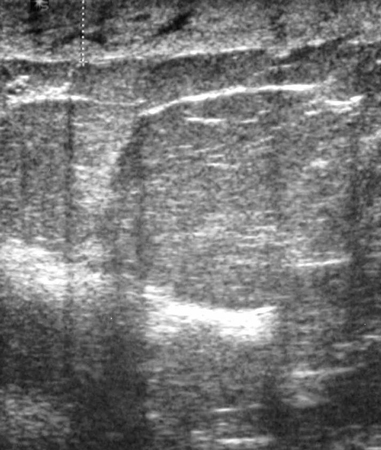

Ultrasonographic image of an invasive carcinoma

Courtesy of Dr Lane Roland, University of Louisville; used with permission